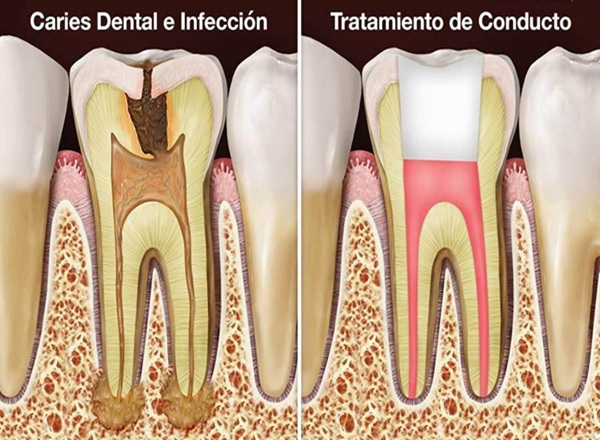

Endodoncia

La endodoncia, también conocida como tratamiento de conductos, permite salvar dientes afectados por caries profundas, infecciones o traumatismos sin necesidad de extracción. Eliminamos el tejido infectado del interior del diente, desinfectamos cuidadosamente y sellamos el conducto para devolverle su función y comodidad.

Es un procedimiento seguro, indoloro gracias a la anestesia moderna y fundamental para evitar abscesos, dolor intenso y pérdida dental.

- ✓ Eliminación de infección y dolor dental

- ✓ Limpieza y desinfección de conductos radiculares

- ✓ Reconstrucción y sellado del diente

- ✓ Duración: 60–90 minutos (según el caso)